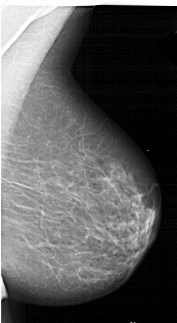

A_1423_1.LEFT_CC

LEFT_CC LINES 5941 PIXELS_PER_LINE 3496 BITS_PER_PIXEL 12 RESOLUTION 43.5 OVERLAY